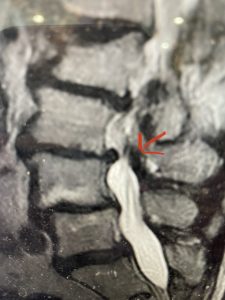

The next patient is a 71 year-old male with a two-year history of low back pain and lower extremity pain, numbness and weakness. His left leg was worse than the right. He had had five epidurals with no improvement. He also had tried physical therapy and medicines but nothing helped. He also felt that over the last three weeks he had gotten worse. He also had recently had some decreased sensation of bladder fullness and difficulty with bowel movements. MRI revealed a very tight L2-5 stenosis with an extruded L3-4 disc fragment (Fig 3).

(Figs 3a) Sagittal (a) and Axial (b) T2-weighted lumbar MRI demonstrating severe spinal stenosis L2-5 (arrow)and extruded disc at L3-4 on axial image (arrow)

(Fig 3b)

He had concentric severe stenosis with severe compression of the lateral recess and foramen at L3-4 secondary to the superimposed disc herniation. The fact that he had gotten worse with subtle cauda equina features with an extremely tight canal, he underwent a decompressive laminectomy. We also augmented his laminectomy with an in situ fusion from L3-5 as he was relatively young, with more time to reform arthritis, and had been unstable enough to extrude a disc fragment. By placing “bone dust” or bone material along the sides of the spine, specifically laying it across the transverse processes after they have been drilled to bleeding bone, you provide an environment where bone formation is induced to connect the segments, stabilize them, and thereby reduce the signal to make more arthritis as that signal is still present despite the laminectomy. What was interesting was that we encountered a large extruded disk fragment that was significantly contributing to his compression which is often not found in patients in this age bracket. Post operatively he had much improvement of leg pain.